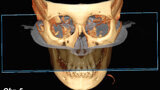

Význam 3D zobrazovacích systémů v současné ortodoncii